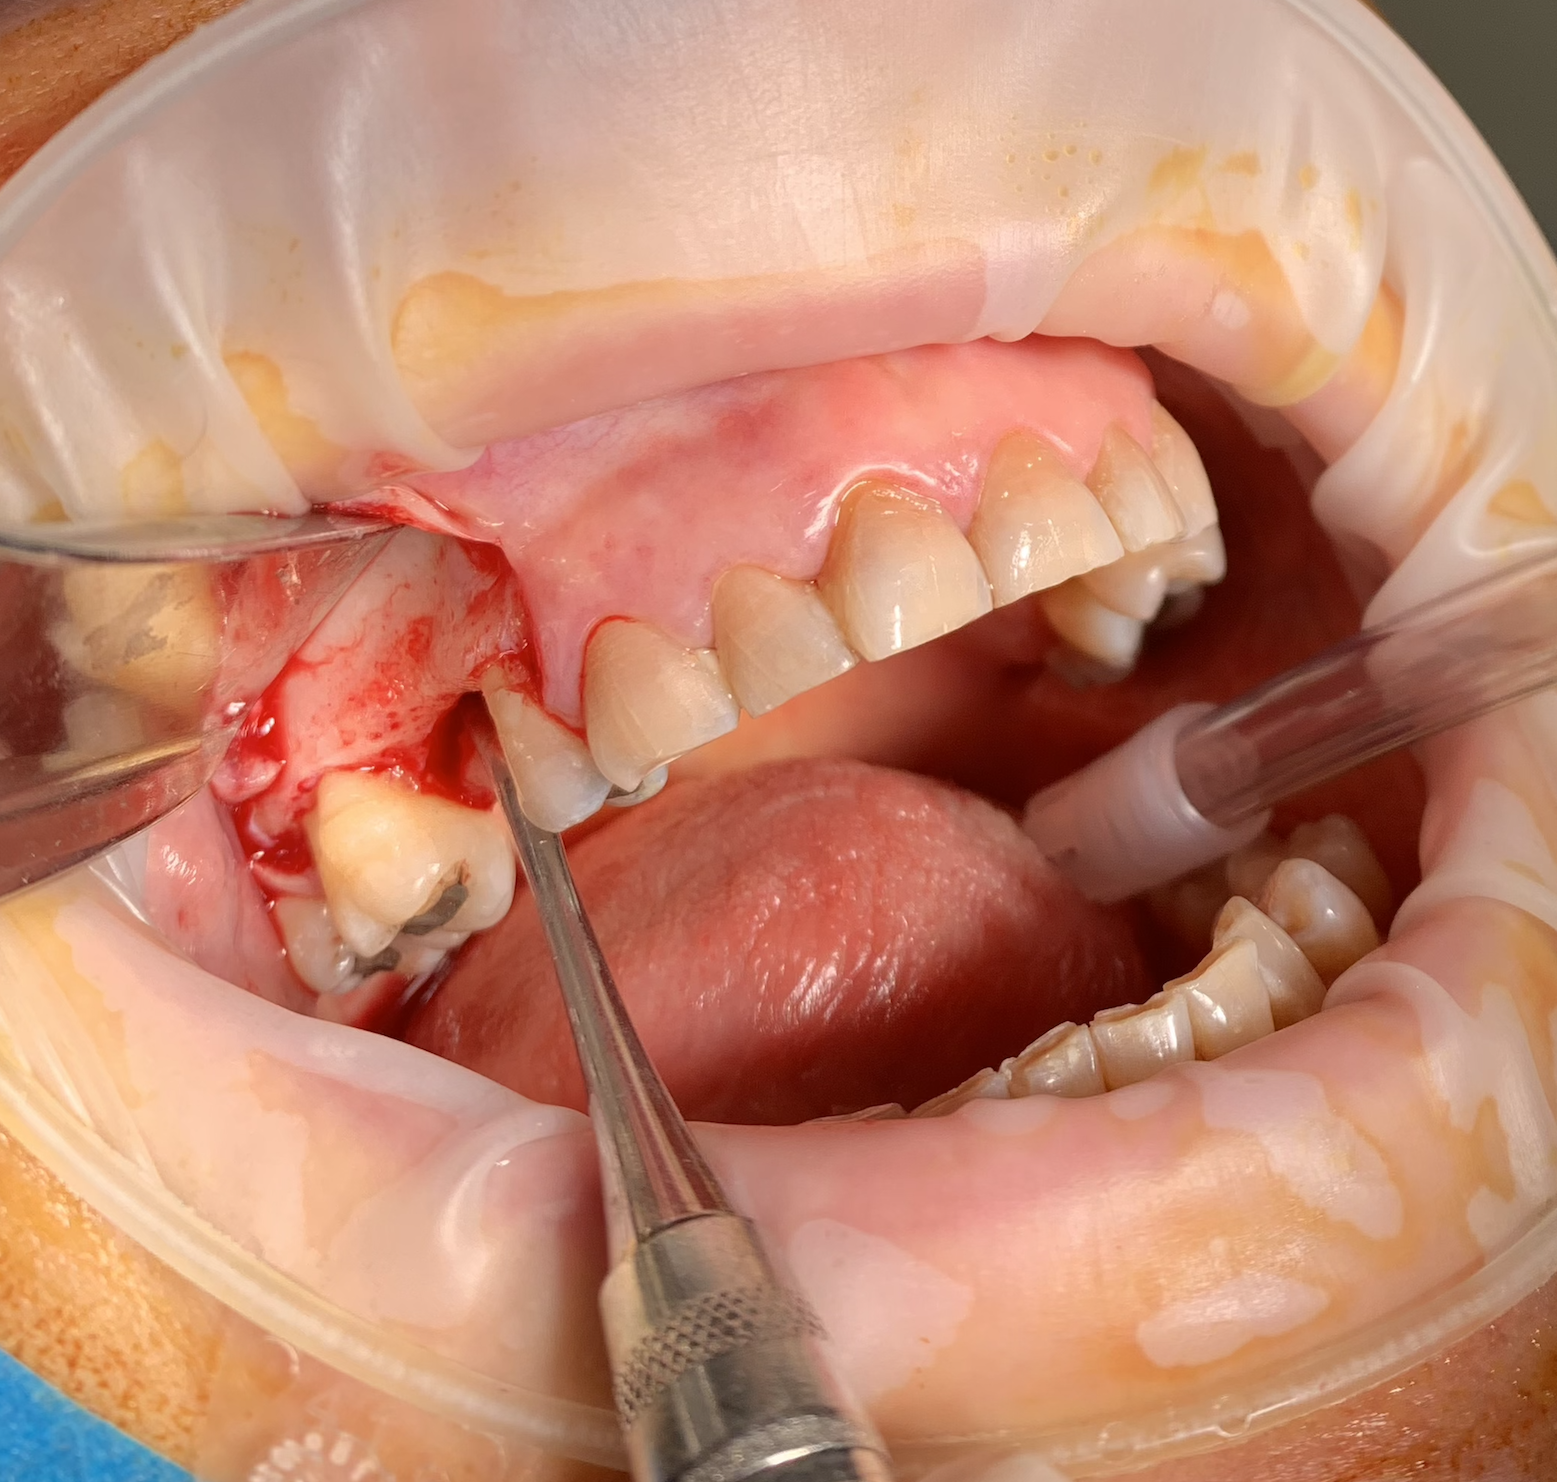

In female patient 51 years old, ASA 1 with tetracycline teeth pigmentation, 1.5 implant placement with simultaneous lateral sinus lift and horizontal bone regeneration sausage technique. At the same time 2.4 implant placement.

1.5 Implant placement, sinus lift and horizontal regeneration + implant 2.4